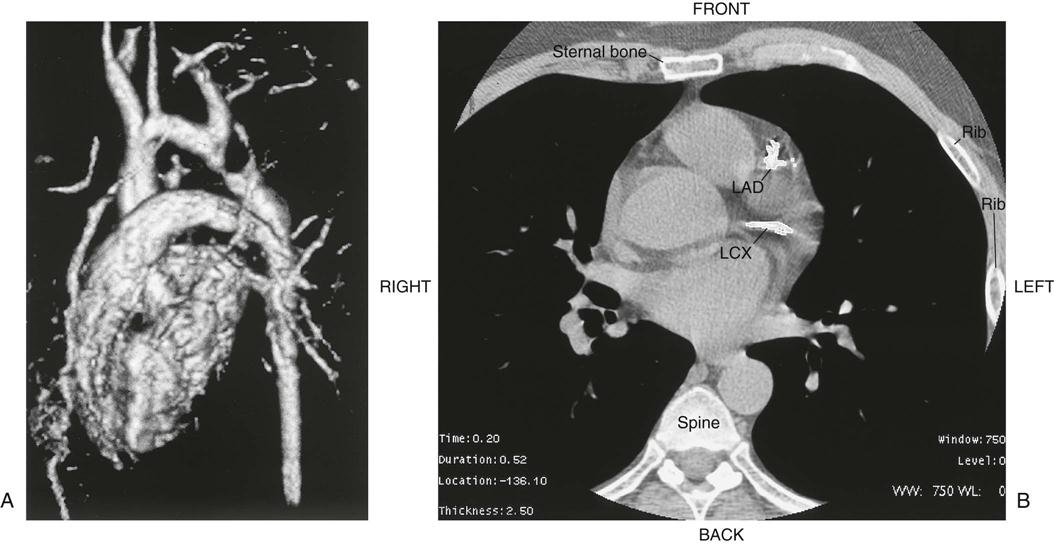

Chest radiography provides information about the size of the cardiac chambers, thoracic aorta, and pulmonary vasculature as well as the presence of calcium in valves, pericardium, coronary arteries, and aorta (Figure 25-8). Lateral chest radiographs of patients with prior sternal surgery show the chest wires and extent of pericardial adhesions. Magnetic resonance imaging (MRI) enables assessment of myocardial viability and also can image vascular structures with MRI angiograms that provide great clarity (Figure 25-9, A). In patients with suspected aortic or other vascular abnormalities, a computed tomography (CT) scan of the chest with intravenous injection of a contrast medium creates x-ray serial “slices” of the body area under study (see Figure 25-9, B). CT angiography is especially useful to image the aorta and the great vessels. CT images of the coronary arteries are used increasingly to identify areas of coronary calcification (shown in Figure 25-9, B), a recognized CV risk factor. One study demonstrated the value of coronary artery calcium scoring to identify patients who may be asymptomatic for CAD, but are at risk for increased mortality (Tota-Maharaj et al, 2012).

CT scans may be contraindicated in very unstable patients because their position in the tubelike scanner makes patient access difficult. Less frequently performed is arteriography with radiographic contrast dye to determine the size and location of the lesion and the site of the intimal tear in aortic dissections (Figure 25-10); digital subtraction angiography (DSA) provides clear images and requires less contrast material.